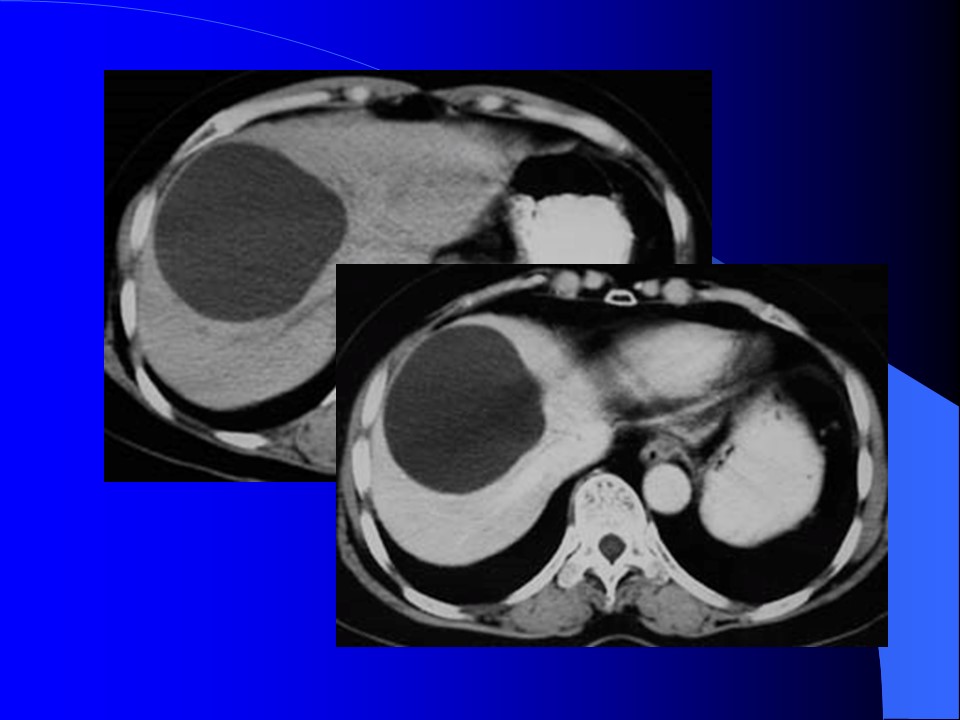

“肝脏常见病CT表现PPT” 的相关文章